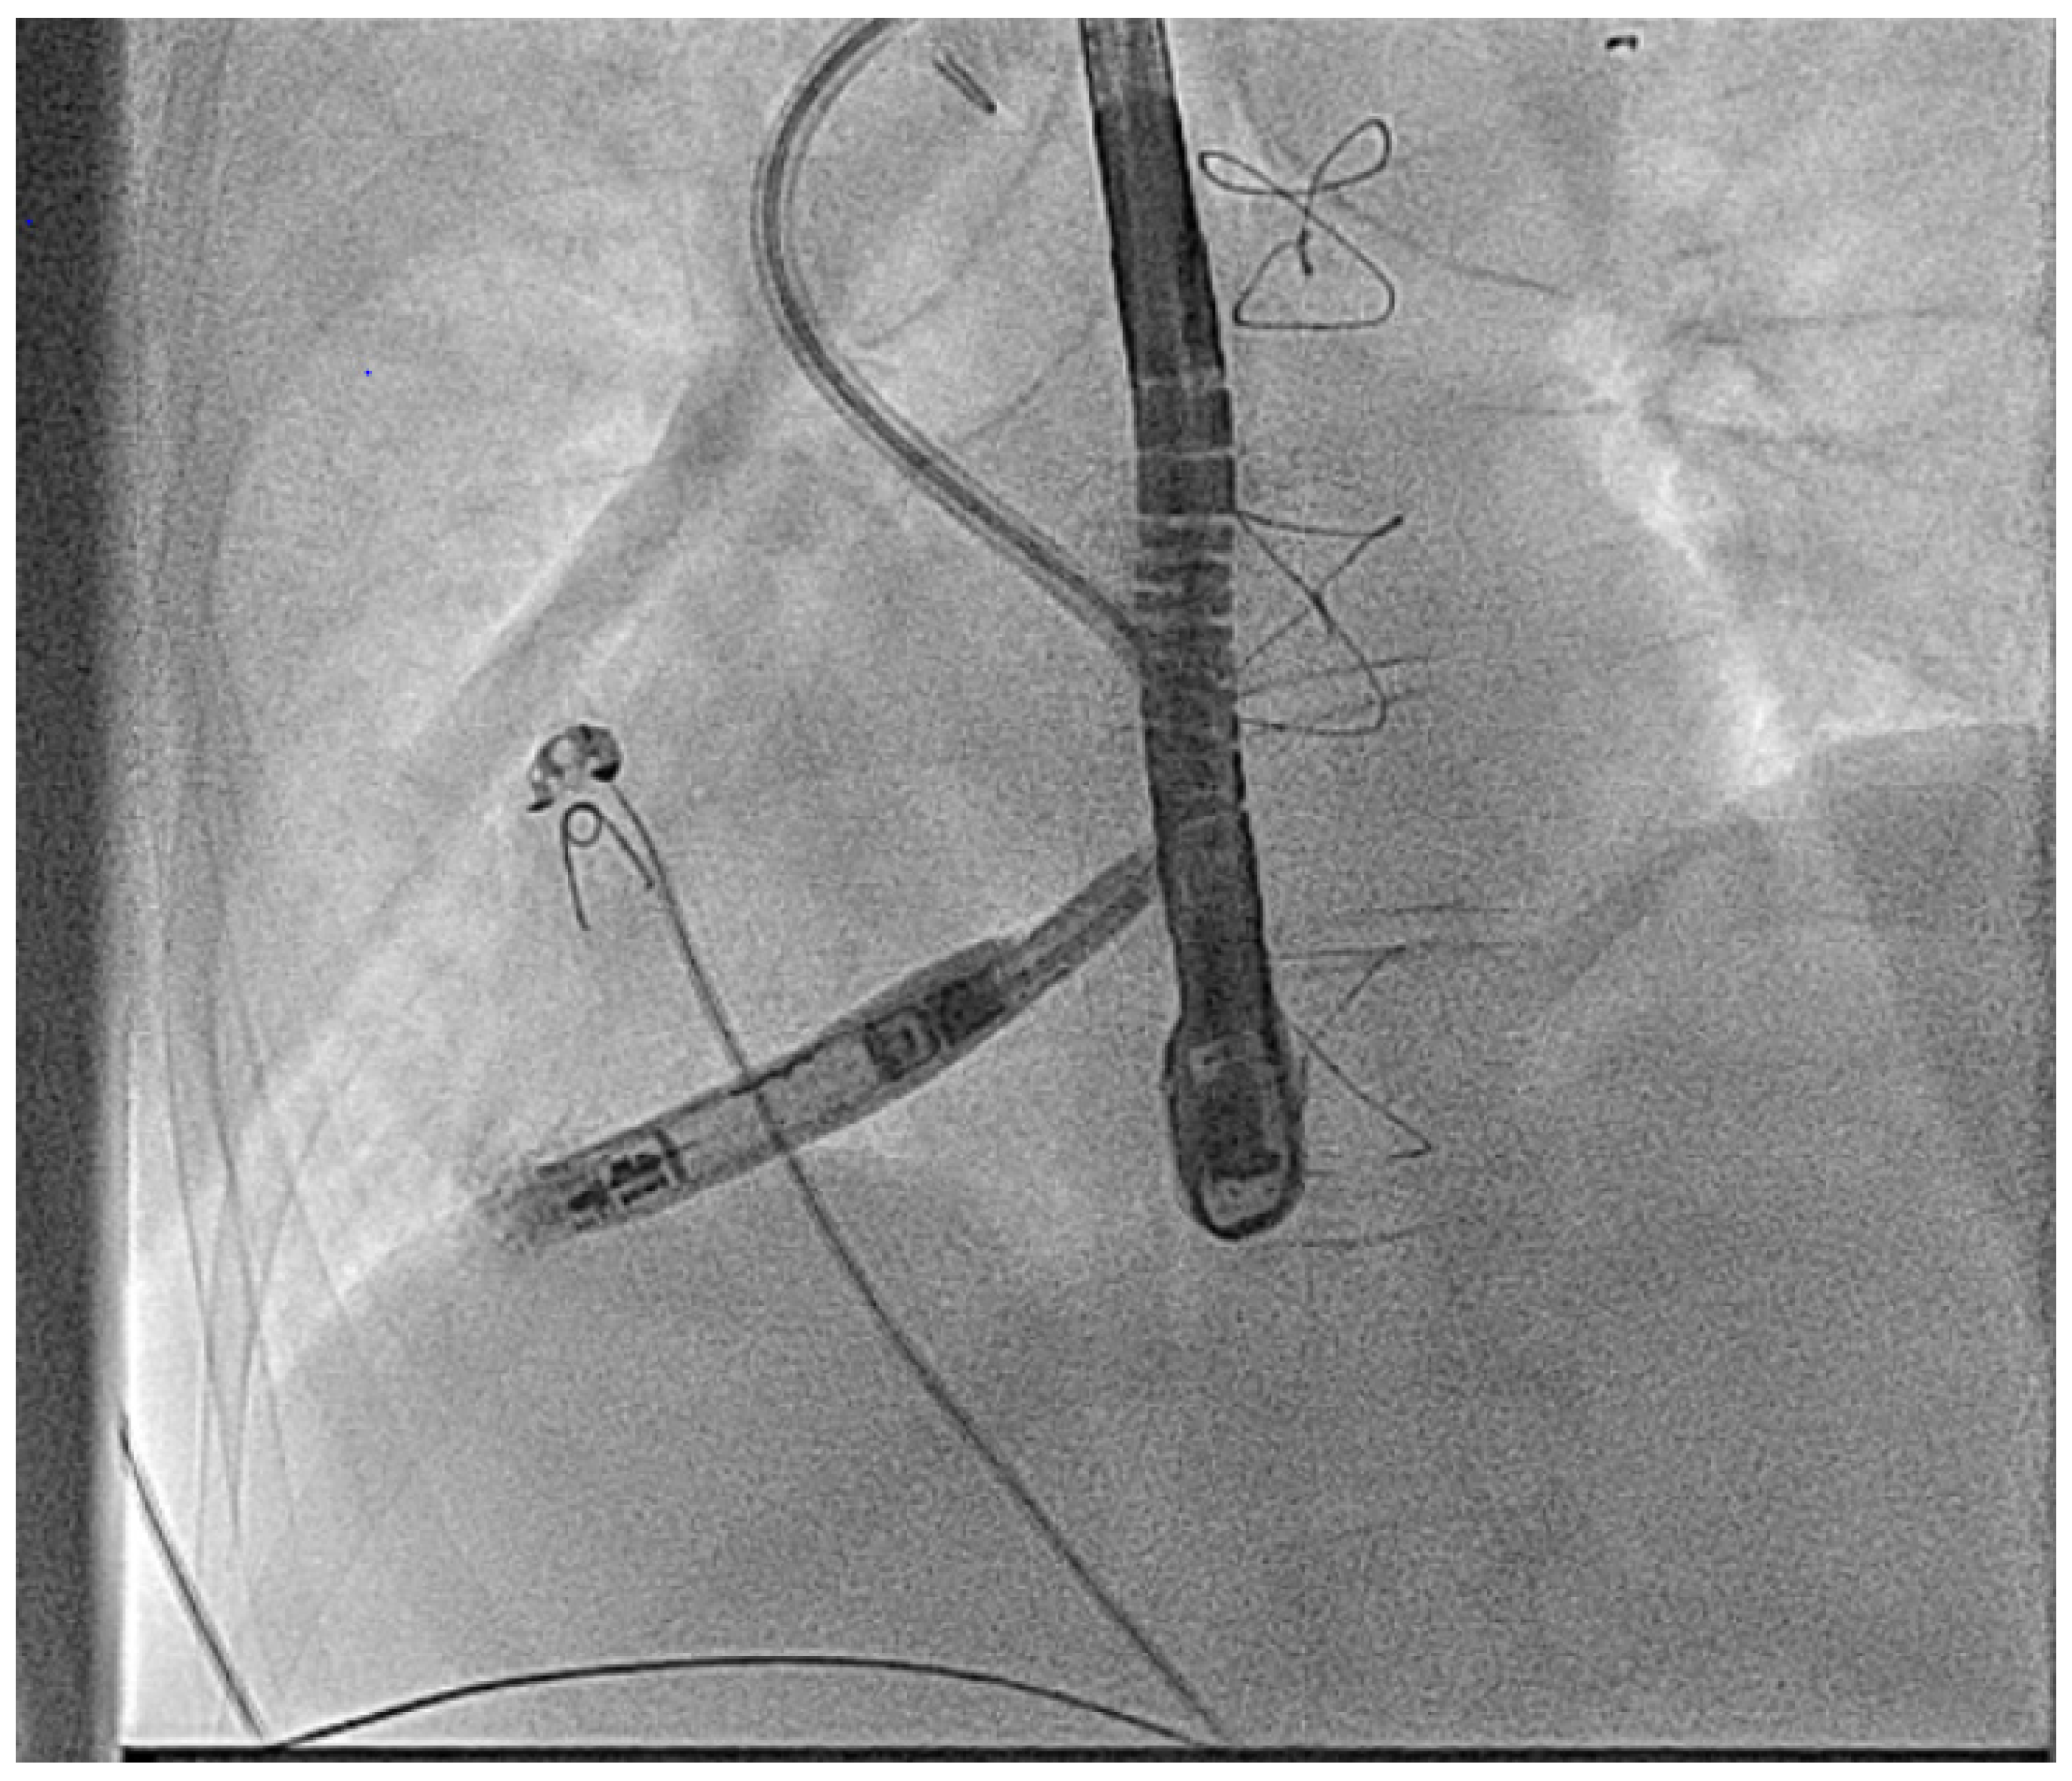

- Calvert, P.; Yeo, C.; Rao, A.; Neequaye, S.; Mayhew, D.; Ashrafi, R. Transcarotid implantation of a leadless pacemaker in a patient with Fontan circulation. Hear. Case Rep. 2023, 9, 53–58. [Google Scholar] [CrossRef]

- Hayle, P.; Altayeb, F.; Hale, A.; Rao, A.; Ashrafi, R. Case report demonstrating novel approaches for leadless pacemaker implantation in the single ventricle heart. Eur. Heart J. Case Rep. 2025, 9, ytaf146. [Google Scholar] [CrossRef]

- Goulden, C.J.; Khanra, D.; Llewellyn, J.; Rao, A.; Evans, A.; Ashrafi, R. Novel approaches for leadless pacemaker implantation in the extra-cardiac Fontan cohort: Options to avoid leaded systems or epicardial pacing. J. Cardiovasc. Electrophysiol. 2023, 34, 2386–2392. [Google Scholar] [CrossRef]